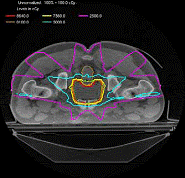

当今进入临床推广应用的最先进的医用电子直线加速器放疗设备。研制IGRT 设备的主要原因是:其一,在单次治疗中,由于病人的自主体内运动,如呼吸可造成心脏器官几个厘米的位置移动,使得病人体内的靶区产生空间位置移动,IGRT 可以动态跟踪这一位置偏移;其二, IGRT 能更有效地进行治疗中或治疗后的质保(QA)和质控(QC),如客观记录放射治疗过程中的含有病人生理组织结构信息的射野图象;其三,在一个疗程或一段时间内,肿瘤的大小和位置会发生改变,IGRT 可以适时调整以适应这些变化。下图显示为通